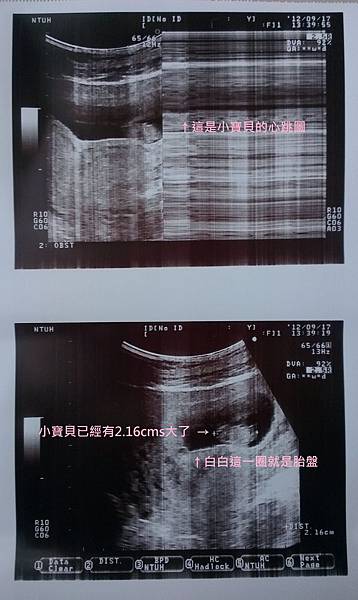

轉頭看著超音波螢幕上的小寶 哇塞才過兩週就從一個小點點變成一顆小婉豆

而且心臟依然有力的蹦蹦跳 真令人欣慰

Dr. Chen說:「妳看從頭到屁股已經有2.16cms囉這是胚囊外面那圈是胎盤,這段時間妳有什麼不舒服的嗎?」

下了檢驗床 Dr. Chen照例將超音波照印出來留給我做紀念